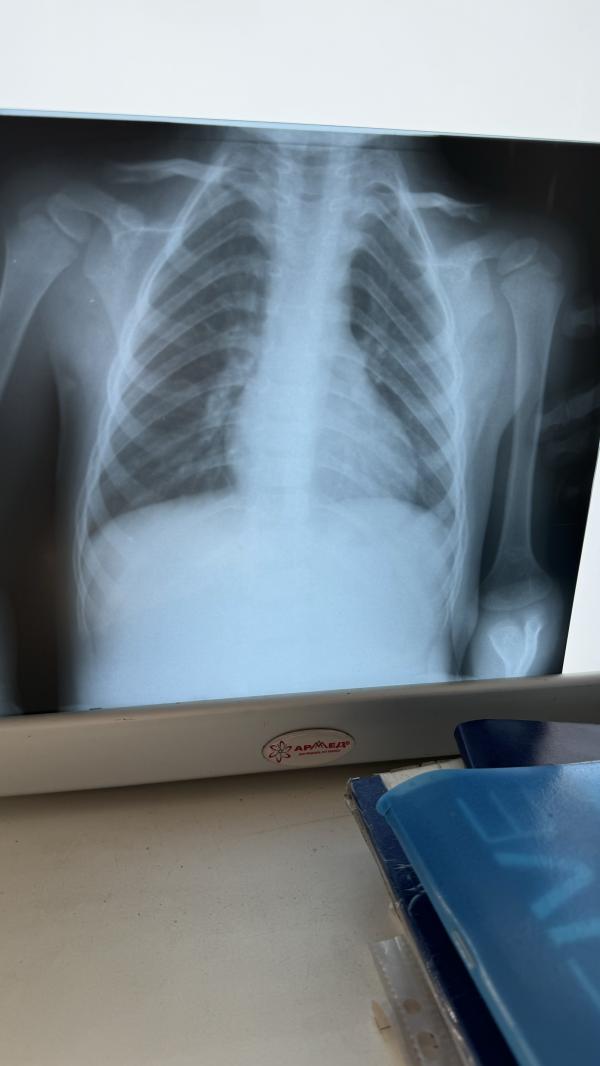

1-фото , когда подтвердили правостороннюю пневмонию

2 фото, когда закончили лечение.

Что на втором фотке? Видно , что прошло пневмония?

Да ,заметно лучше стало

Да лучше то стало. Альхамдулиллах

Но полностью не прошел как будто)

Остаточный чтоли 🥲